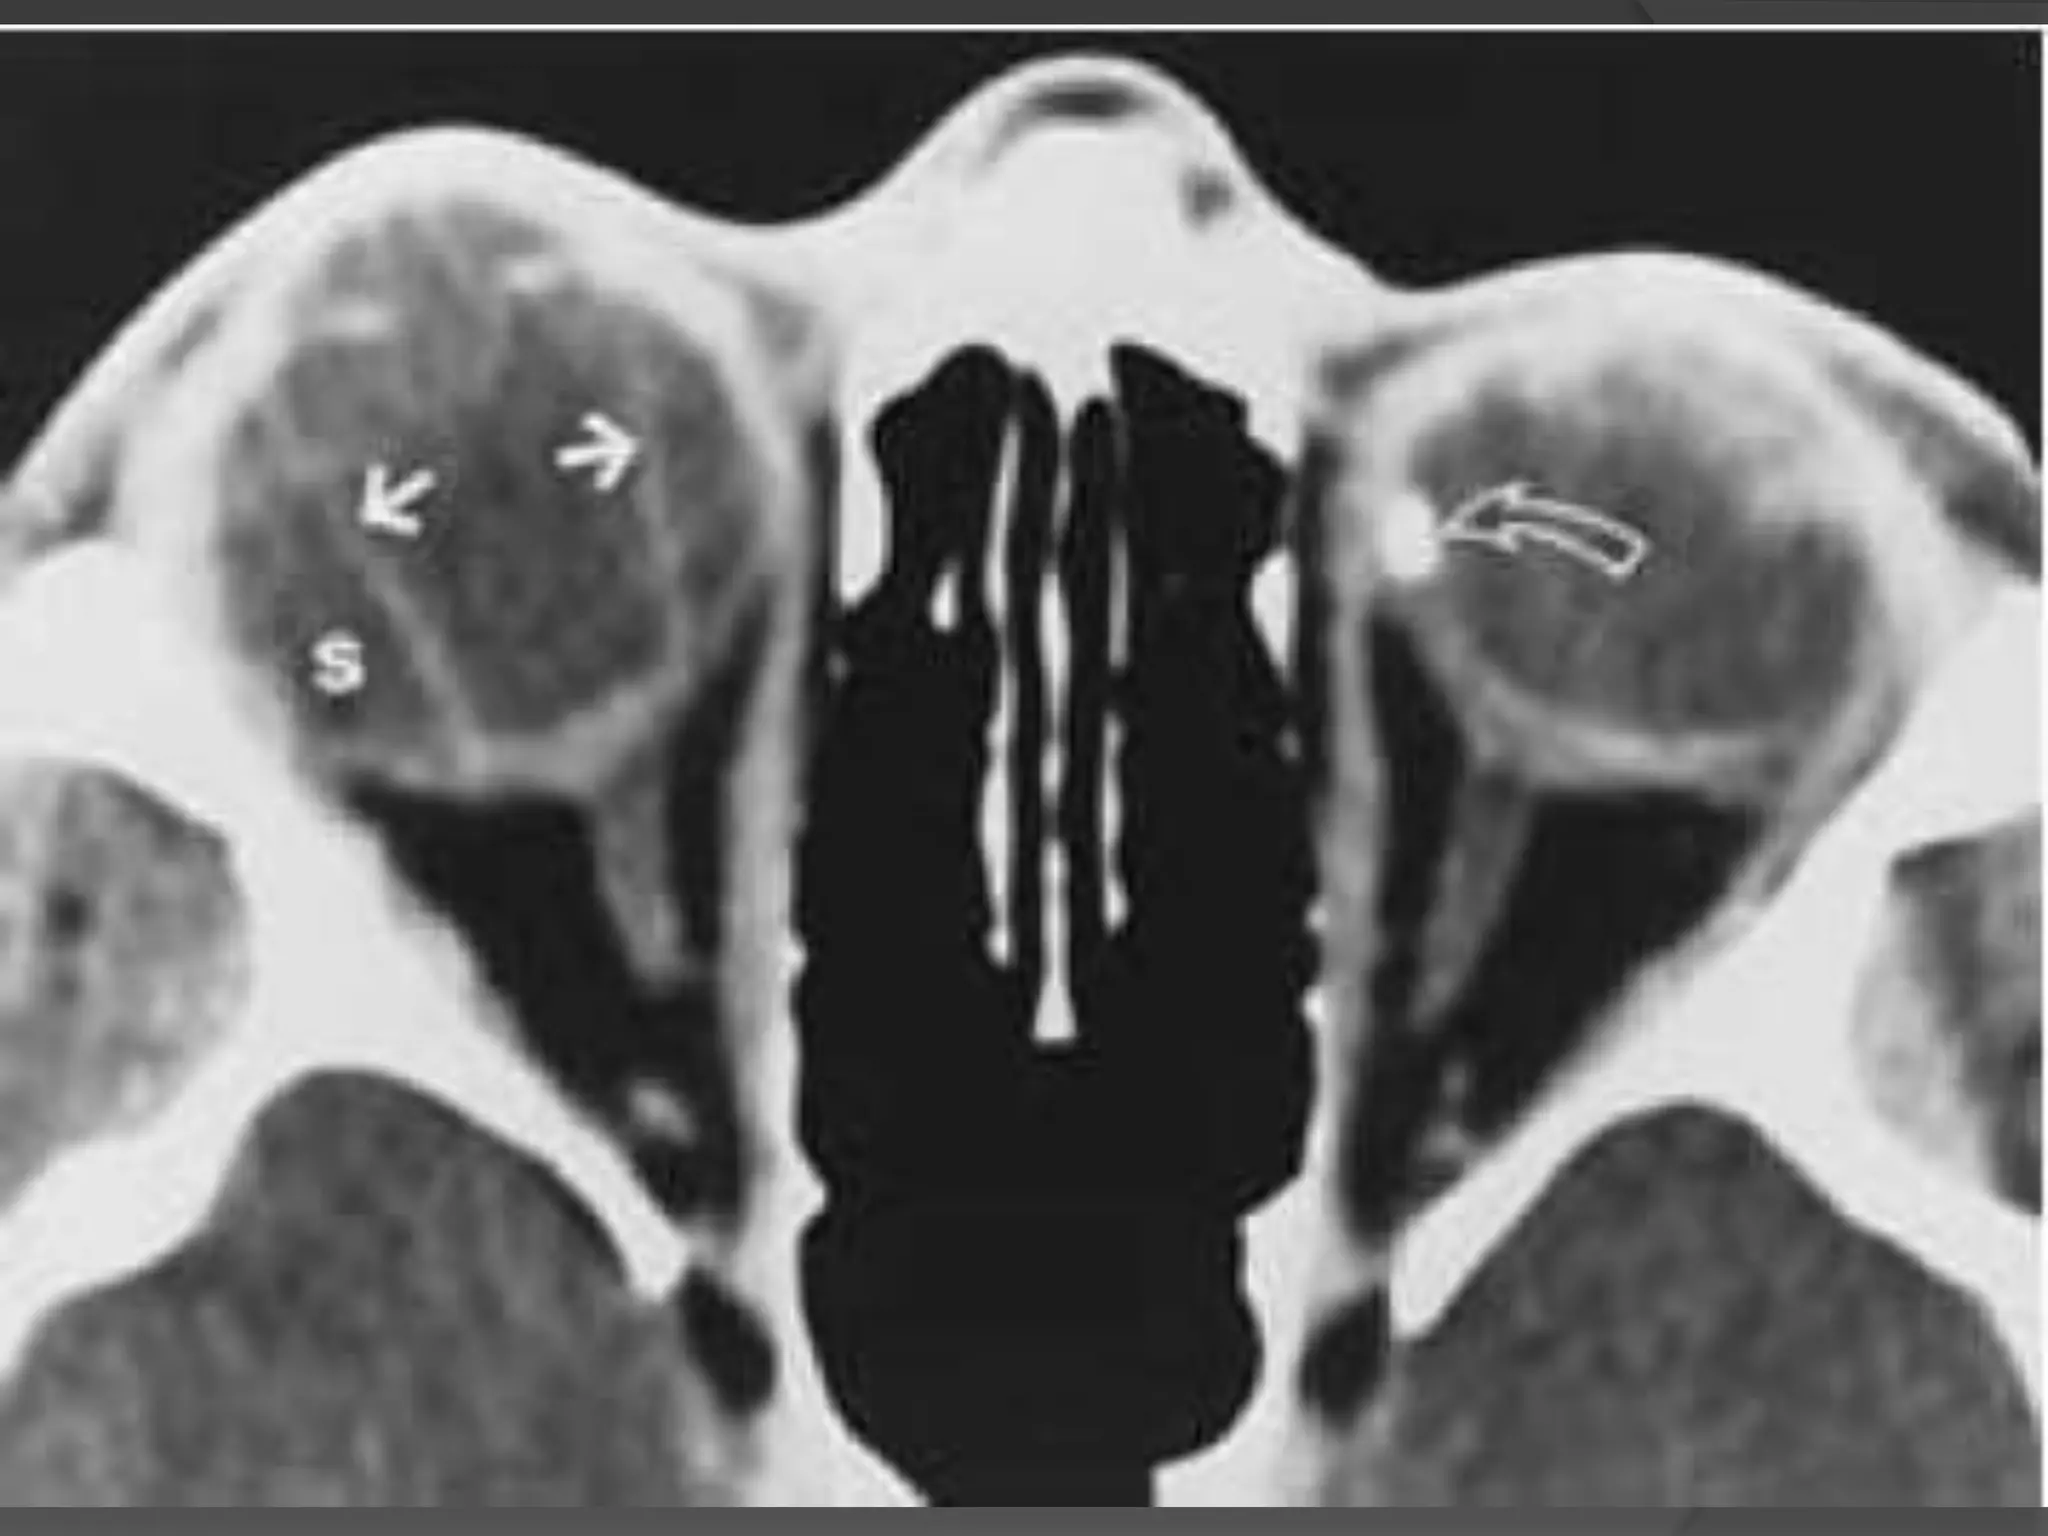

• #15 Serous choroidal detachment. Axial CT scan shows two prominent linear images (solid arrows) in the right eye. Because of the anchoring effect of posterior ciliary arteries and nerves, detached leaves of choroid usually do not appear to converge at the disc, unlike retinal leaves in retinal detachment. The suprachoroidal space (S) is isodense with vitreous, indicating serous choroidal detachment. The enlarged right globe results from known congenital glaucoma. Note the postsurgical changes in the left eye and the scleral-encircling silicone band (curved arrow).